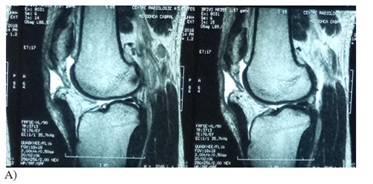

Figure 1 Case: Patient 28 years old male, 10 day history of sports injury with complete patella tear accident: we proceeded to a repair using trans-osseous patella suturing with vicryl 2 and reinforcement semitendinosus.

A-T2 sagittal section